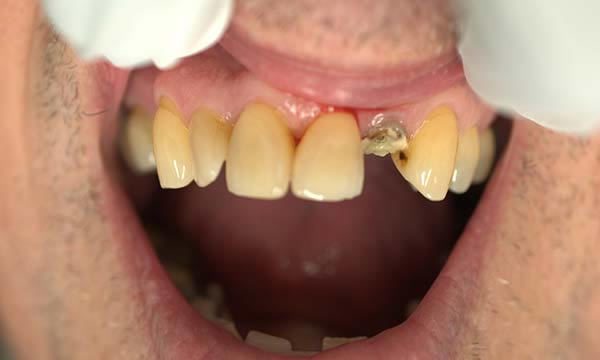

This gentleman came to see me after his crown decorated. He was fed up with being called a pirate by his grandchildren and decided to do something about the gap.

Due to an absence of infection and an atraumatic extraction, the removal of the tooth was followed by immediate implant placement. The implant was restored with an Atlantis abutment and bonded crown.